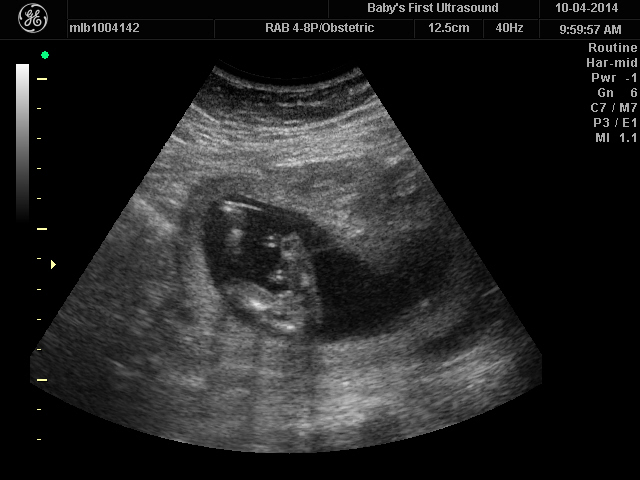

Attachment 21524Attachment 21525

I'd lean girl I think GL

Not seeing much so leaning girl too

Girl

Looking pink.

Thinking pink!

Gurl Sent from my iPhone using Tapatalk